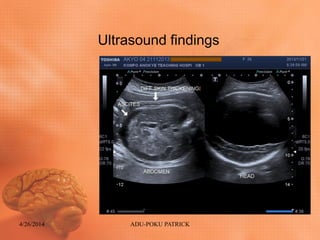

Ultrasound findings

Ultrasound findings: ABDOMEN

• Diffuse skin thickening (Generalized body

Edema)

• Fetal Ascites

• Intact diaphragm

• Normal cord insertion

• Intact stomach

• Hepatomegaly

• Urinary bladder intact